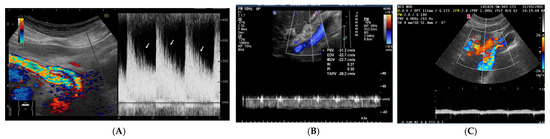

Assessing Venous Congestion in Acute and Chronic Heart Failure: A Review of Splanchnic, Cardiac and Pulmonary Ultrasound: Part 1: Conventional B-Mode, Colordoppler, and Vexus Protocol

Background/Objectives: Heart failure (HF) causes systemic and regional haemodynamic alterations that extend beyond the heart, profoundly affecting splanchnic circulation. Venous congestion is a hallmark of heart failure (HF) and a major determinant of clinical deterioration and multiorgan dysfunction. The splanchnic venous system—comprising [...] Read more.

Background/Objectives: Heart failure (HF) causes systemic and regional haemodynamic alterations that extend beyond the heart, profoundly affecting splanchnic circulation. Venous congestion is a hallmark of heart failure (HF) and a major determinant of clinical deterioration and multiorgan dysfunction. The splanchnic venous system—comprising the portal, hepatic, and renal veins—acts as a key reservoir for intravascular volume redistribution. Conventional ultrasound (US), using grayscale and Doppler imaging, offers a direct, non-invasive approach to visualize these haemodynamic changes. This review, Part 1 of a two-part series, summarizes the current evidence and clinical applications of conventional US for assessing splanchnic, cardiac and pulmonary vascular alterations in patients with HF. Methods: A systematic review was performed in PubMed, Embase, and the Cochrane Library up to current date, following PRISMA 2020 guidelines. Eligible studies included adult human investigations evaluating splanchnic vascular changes in HF using B-mode, color Doppler, or pulsed Doppler ultrasonography. Exclusion criteria were pediatric, animal, or non-English studies and non-standard imaging methods. Data on ultrasonographic parameters, haemodynamic correlations, and prognostic value were extracted and qualitatively synthesized; Results: A total of 148 eligible studies (n ≈ 7000 patients) demonstrated consistent associations between HF severity and alterations in splanchnic, cardiac and pulmonary flow. Findings included increased bowel wall thickness, portal vein dilation with elevated pulsatility, and monophasic or reversed hepatic vein waveforms, all correlating with higher right atrial pressure and adverse clinical outcomes. The integration of these parameters into the Venous Excess Ultrasound (VExUS) framework enhanced detection of systemic venous congestion, in addition to the study of the cardiac and pulmonary circulation. Conclusions: Conventional ultrasound assessment of splanchnic vasculature provides valuable, reproducible insight into systemic congestion in HF. Incorporating hepatic and portal Doppler indices into standard evaluation protocols may improve risk stratification, optimize decongestion therapy, and guide management. Further prospective randomized and outcome-driven studies are required before VExUS-based therapeutic thresholds can be universally recommended and define prognostic thresholds. Full article